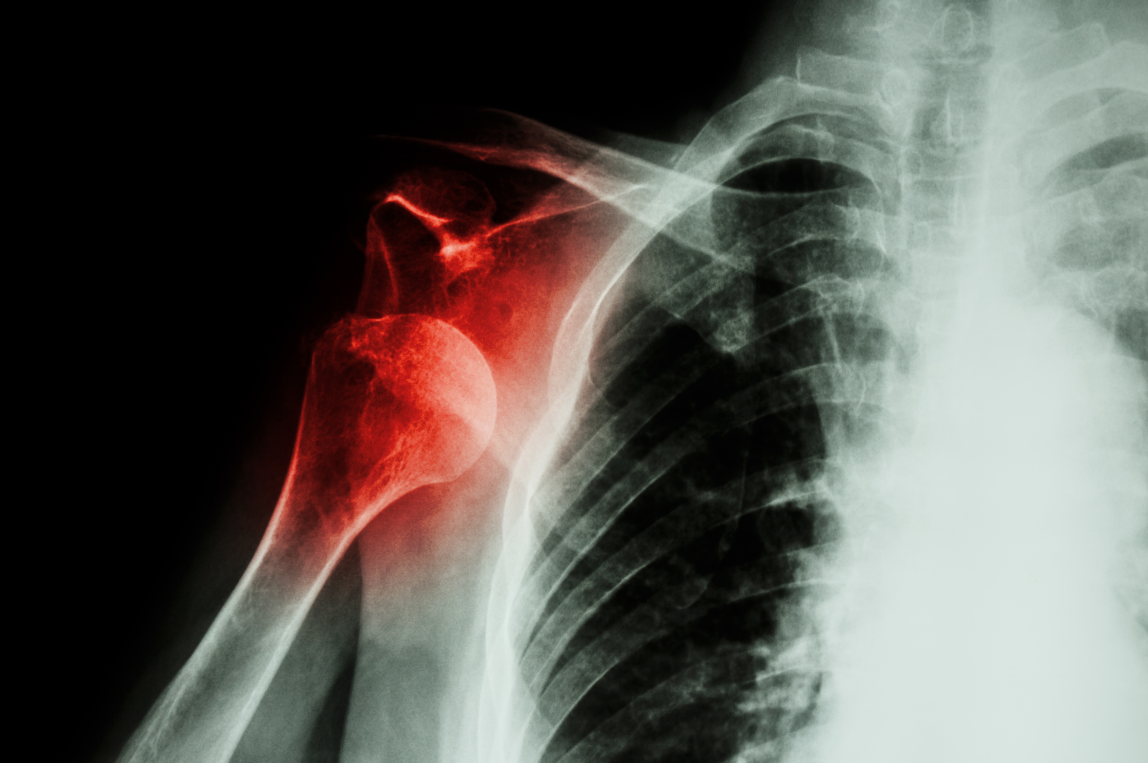

肩峰骨折是一种临床非常少见的骨折类型,指肩胛骨外侧与肱骨形成关节突出的部分出现的骨折,多由于直接暴力引起。